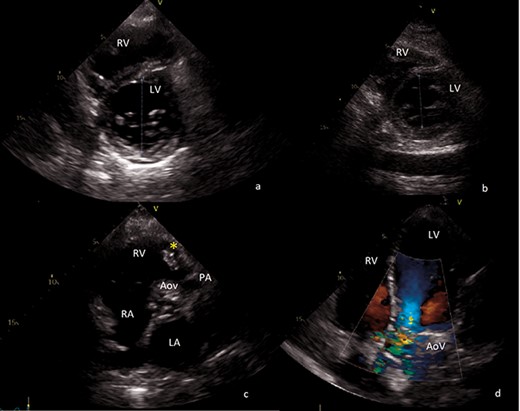

Both right and left ventricle grossly dilated due to excessive volume overload (end-diastolic left ventricle diameter of 68 mm) (Fig. 1a).

Transthoracic echocardiography images. (a) Preoperative short axis view of left ventricle. End-diastolic left ventricle diameter of 68 mm. (b) Postoperative short axis view of left ventricle. End-diastolic left ventricle diameter of 43 mm. (c) Sizable vegetation (yellow asterisk) of about 4 cm provoking right ventricular outflow obstruction. (d) Four-chamber view, showing severe aortic regurgitation. AoV aortic valve; LA left atrium; LV left ventricle; PA pulmonary artery; RA right atrium; RV right ventricle.